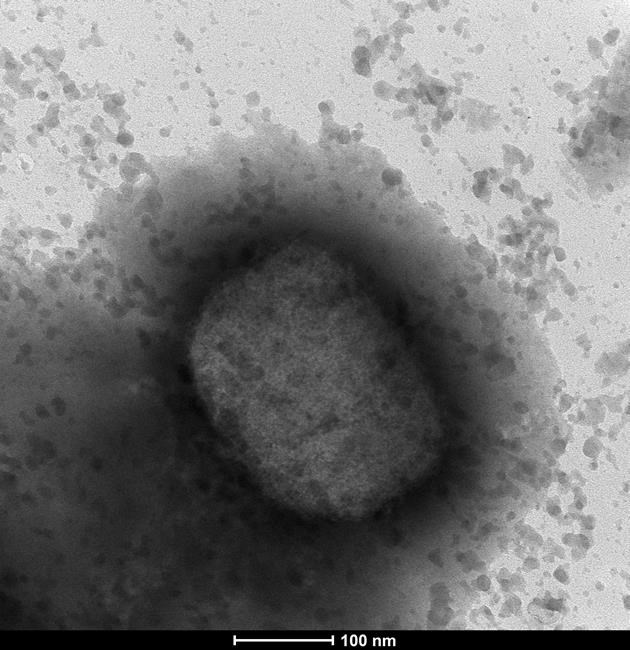

OTTAWA – The Public Health Agency of Canada is warning travellers to be extra careful abroad because of the potential threat of catching monkeypox.

The virus, typically only found in West and Central Africa, has cropped up around the globe with cases in Canada, the United Kingdom, Spain and more than two dozen other countries.

Monkeypox spreads mainly through close contact with the virus on other humans or objects such as bed linens. While it can be fatal, it is most often not, causing symptoms such as fever, headache and muscle aches, and pox-like lesions on the skin.